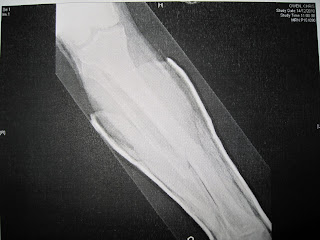

A very pleasant and friendly young lady wheeled a computer

into the ward and showed me the Xrays and the CT scans:

Tibia fractured with bits of bone surrounding the break.

Fibula shattered into 3-4 pieces.